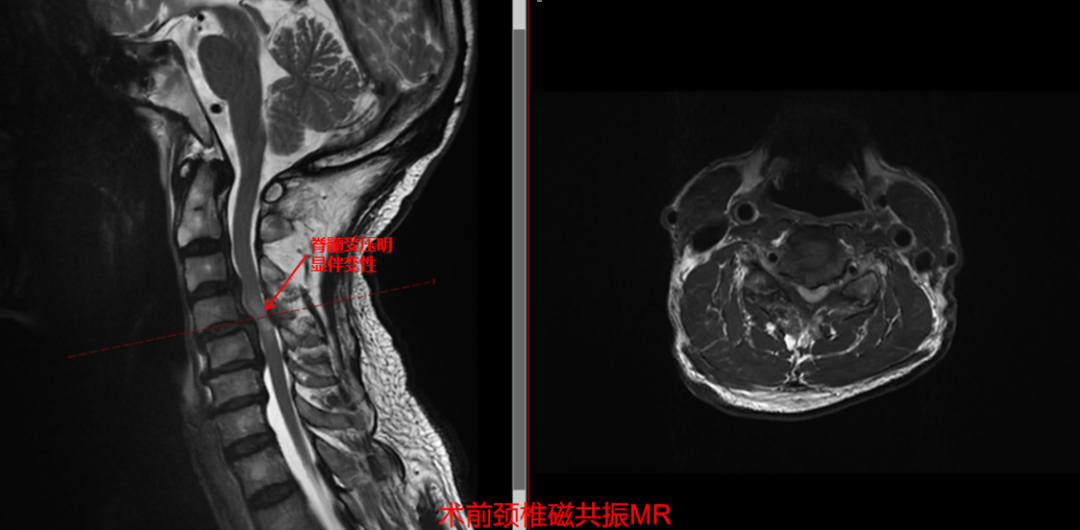

术前影像学提示:多节段颈椎滑移、颈椎间盘突出、椎体后缘骨赘增生、颈 3-颈 5 脊髓受压严重伴脊髓信号改变;其中整个颈 5 椎体后方疑似游离髓核组织,为手术的关键难点。